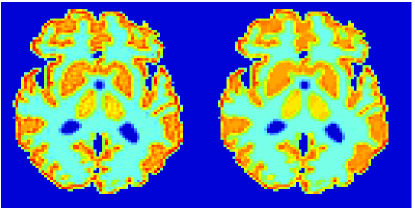

In the images shown in the figures we illustrate the calculated uptake rates of the FDG. Images for the CMRGlc can be obtained by directly scaling . In figure 1 we compare the result of using Patlak and TV-Patlak for estimating the uptake rates with respect to no noise, noise in the input function, Poisson noise in the sinogram, and finally with respect to the case in which the irreversibility assumption is violated but without noise in the sinogram or input data. In each case the histogram of the relative errors is given on the left, the Patlak image in the middle and the TV-Patlak on the right. The different scales in the histograms are due to the total number of results illustrated. When there is no noise (triples and ) the histogram illustrates results over all voxels but only one simulation, while for the noisy simulations the results are for all voxels over all realizations of the noise. The TV-Patlak images are more homogeneous in all cases and the relative errors are smaller. The figures clearly show the improvements of employing the TV-Patlak method as compared to using Patlak independently for each voxel. This is confirmed in figure 2 in which images with noise in the sinogram, positive and different noise levels in the input function are shown.

In figures 3 and 4 we illustrate the uptake rates and relative error in the uptake rates, respectively, calculated by Patlak, TV-Patlak, Patlak-GF and Patlak-MF for one simulated data case , i.e. , noise in the input function and Poisson noise in the sinograms. The uptake rate image generated by Patlak-MF is visually smoother than that by TV-Patlak, but the equivalent histograms show that the relative error is higher for Patlak-MF than for TV-Patlak; the Patlak-MF image is over-smoothed.